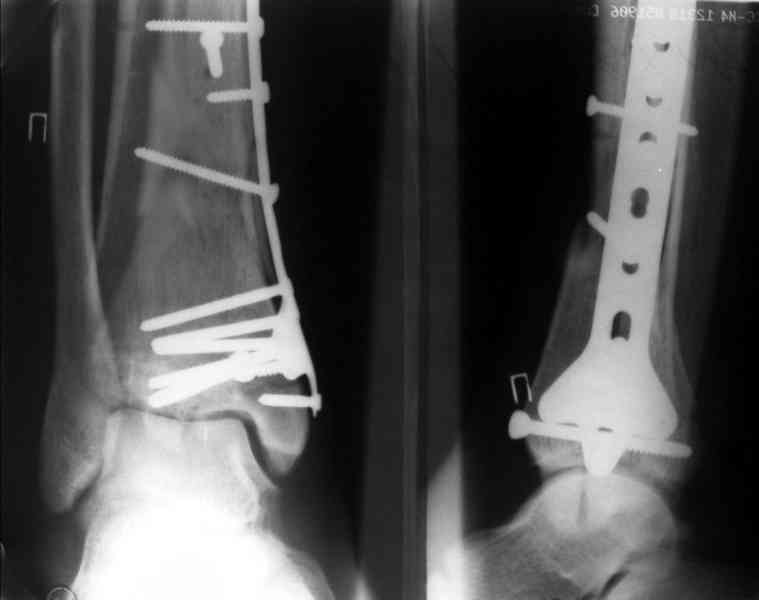

Это типичный перелом пилона, который надп лечить только открыто.Извини те что опоздал к обсуждению, но даже если вы уже оперировали больного по Илизарову это даже лучше.Посылаю картинки.

Посмотрим вроде прошло если понравится напишите расскажу как это сделать.По принципам АО кстати при поступлении сначала восстанавливают длину малоберцовой кости фиксируют пластиной 1/3 трубки потом накладывают аппарат наружной фиксации и через 7-10 дней открыто восстанавливают большеберцовую кость.С уважением Дрягин

На рентгенограммах типичный перелом пилона по типу С-3. есть опыт до 100 открытых опреаций у нас в клинике. 20 примерно в год. Принцип один -все внутрисуставные переломы нуждаются в открытой репозиции и внутренней стабильной фиксации. При поступлении КТ не надо, так как получается только нагромождение костей. Истинной картины нет. Главное восстановить длину малоберцовой кости - это ключ к успеху. При поступлении меньше всего надо думать о сосудистых расстройствах, т.к. сама операция и репозиция даже сначала частичная даёт улучшение сосудитых нарушений. Причём очень быстро. Операция в 2этапа. При поступлении доступ позади наружной лодыжки, причём обязательно. После этого репозиция малоберцовой кости и фиксация пластиной 1/3 трубки под винт 3,5. Дренаж и любой аппарат наружной фиксации. Затем после спадения отёка на 5-7-10 день аппрат снимается и дугообразный разрез спереди от медиальной лодыжки 10-12 см. Главной чтобы расстояние между 1 и вторым разрезом было не меньше 7-8 см. Тогда не будет некрозов лоскутов. Таранная кость используется как матрица на неё укладываются отломки и фиксируются пицами. Ренг-контроль. Отломки лежат все отдельно, но ничего не высыпется. При переломах С-3 всегда нужна костная пластика (из крыла). Фиксация пластиной лист клевера простой или LCP. Гипс не нужен. Дренаж до 48 часов. Операция длится 3-4 часа обязательно без жгута. Посылаю примерно такой же случай.

Посылаю результат лечения предыдущего больного через год.